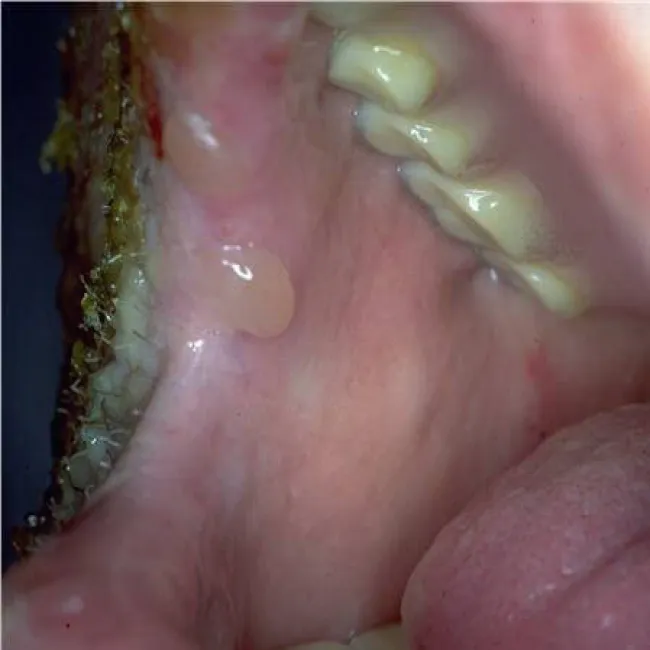

Pęcherz w jamie ustnej

Pemfigoid pęcherzowy

Jama ustna